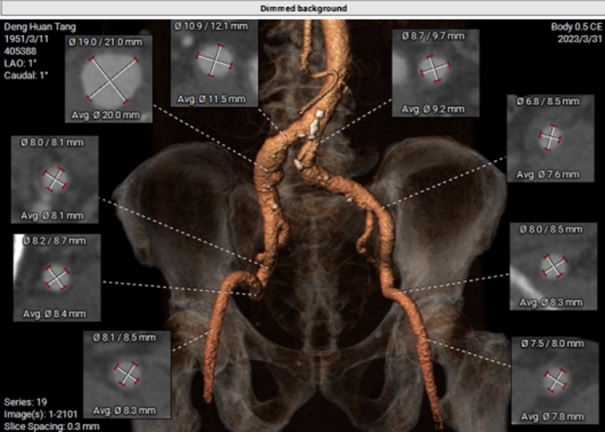

经过手术团队反复评估和研讨后,最终考虑选用右股动脉为主入路,导丝过瓣后,植入VitaFlow Liberty TAV30瓣膜,用DSR30电动可回收输送系统确保瓣膜的精准定位和释放,术后结合造影和超声,再评估是否需要瓣中瓣做为预案。